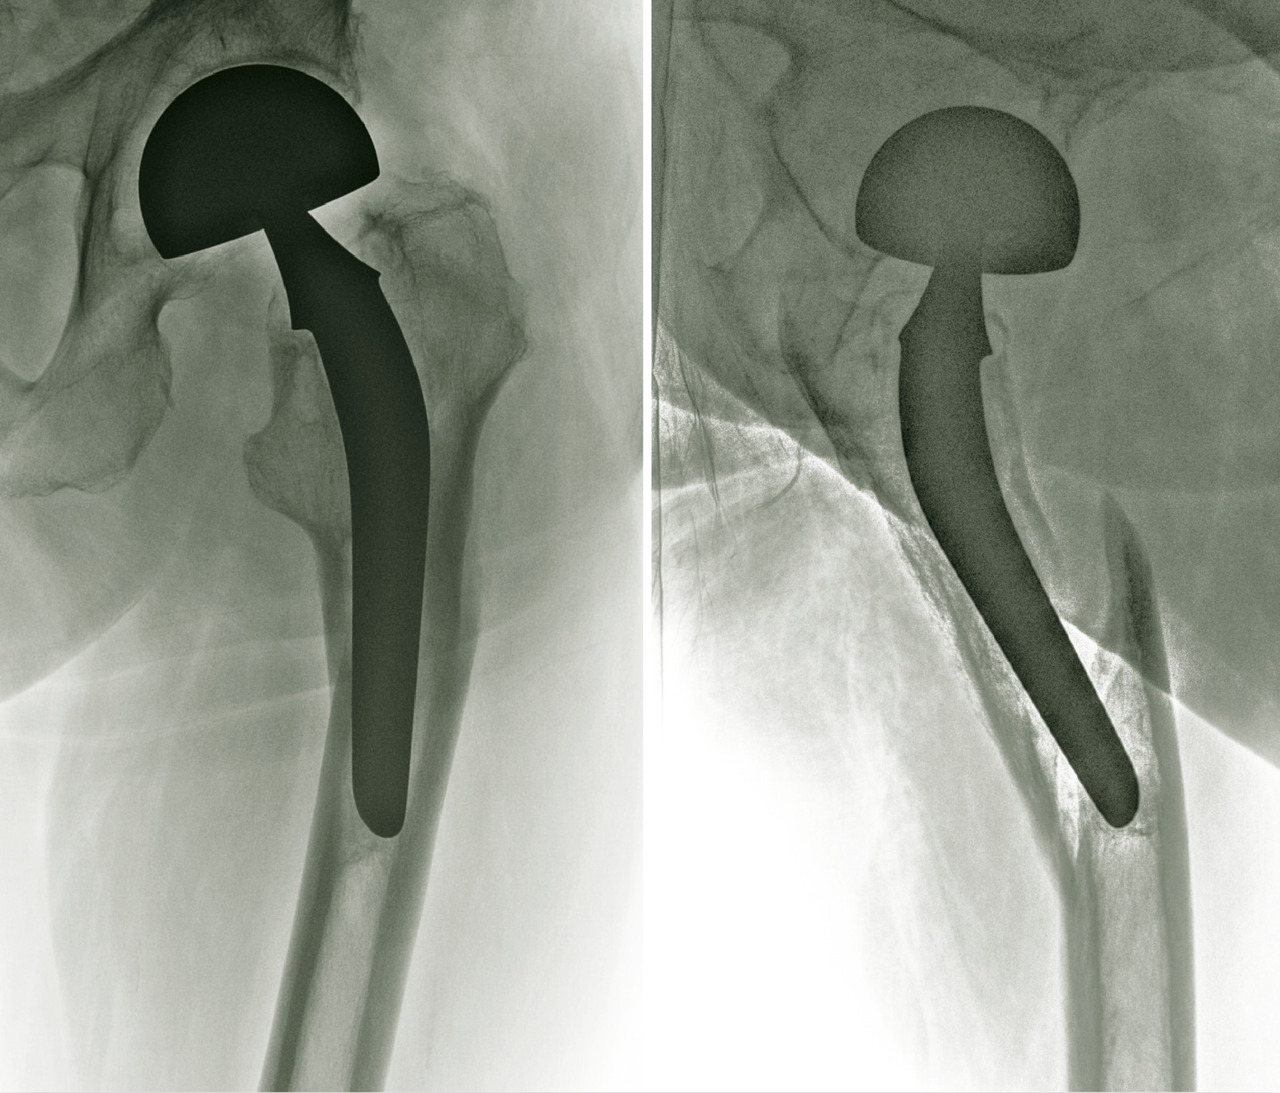

En cas de fracture cervicale vraie Garden III ou IV, le risque de nécrose est important, et il est préférable de s’orienter vers un remplacement prothétique (fig. 14). Il peut s’agir d’une prothèse céphalique où la prothèse remplace uniquement la tête fémorale. Il peut s’agir d’une prothèse intermédiaire qui remplace la tête fémorale mais avec un système de double glissement qui améliore la stabilité de l’implant et diminue les risques d’usure de l’acetabulum. Il peut s’agir d’une prothèse totale de hanche. L’utilisation ou non du ciment pour la fixation de la prothèse ne fait pas consensus dans la littérature, chaque méthode ayant ses avantages et ses inconvénients. Toutefois, chez les patients jeunes, en général de moins de 50 ans, malgré les risques de nécrose, l'ostéosynthèse est conseillée, même dans les fractures Garden III et IV.